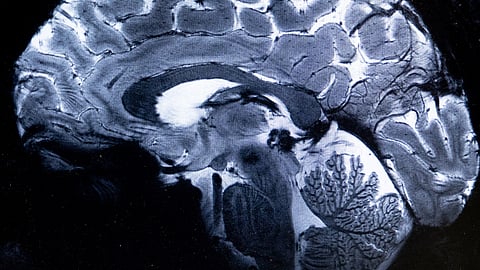

Brain tech breakthrough restores ALS patient’s voice

Casey Harrell, diagnosed with ALS in 2019, experienced a breakthrough thanks to brain-computer interface technology developed at UC Davis. This innovation enabled Harrell to communicate with his own voice, providing a profound sense of normalcy and enhancing his human connections. Despite the technology's bulkiness and slower speech pace, it offers hope for improved communication. Harrell's journey highlights the promise of neuroprostheses in transforming lives and advancing medical technology.